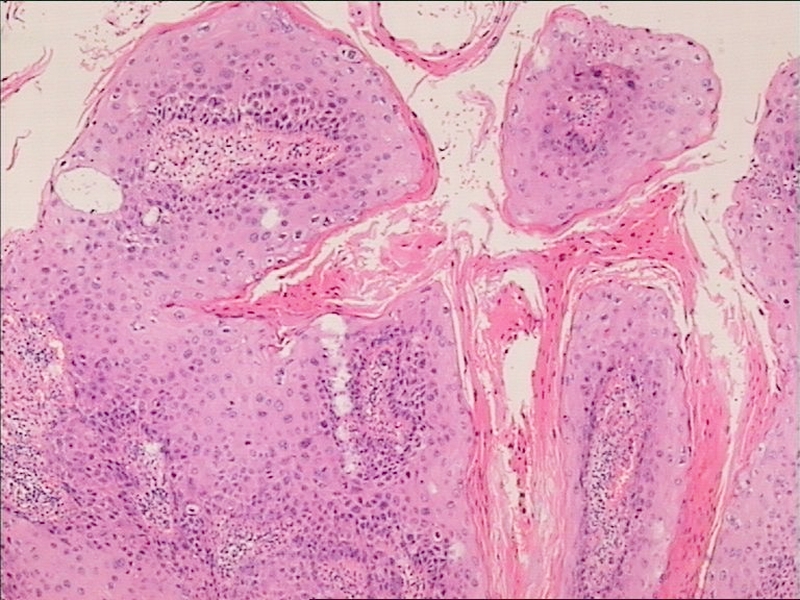

Карнификация Легкого: Микропрепараты и Диагностика

Раздел: Калейдоскоп образов